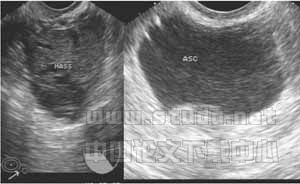

2.1 超声检查声像图特点 (1)子宫多轻度增大,子宫内膜多不同程度增厚,宫内均未见妊娠囊,6例可见壁薄单环状“假妊娠囊”。(2)一侧附件区包块。本组42例均发现左或右侧附件包块,包块最小1?5cm×1.2cm,最大6.5cm×3.2cm。包块均为形态不规则、边界不清楚、回声紊乱的混合回声光团[1],见图1。(3)陶氏窝、包块周围或子宫四周可见多少不一的液性暗区,量多者,肝肾间隙、脾肾间隙及腹腔两侧亦可见不规则液性暗区,暗区中多有密集点状回声,见图1。

3.1 宫外孕破裂出血的声像图 宫外孕发生率占妊娠的0.5%~1%,其中95%为输卵管妊娠[1]。常与输卵管炎、输卵管手术后输卵管不同程度粘连、受精卵移行不畅有关。输卵管妊娠时由于缺乏完整蜕膜,孕卵植入后,其绒毛借蛋白分解酶的作用直接侵蚀管壁肌层,因输卵管管壁薄弱,不能适应受精卵的发育,当受精卵发育到一定程度后,常引起流产或破裂[2]。如本文手术证实的36例宫外孕破裂中,输卵管破裂就有33例,占92%(33/36)。由于输卵管肌层血管丰富,短期内即可大量出血使患者陷入休克。由于破裂口周围形成凝血块或未凝血液,从而超声表现为形态不规整、边界不清楚、回声紊乱的混合性包块,并有盆腔积液,积液中含血细胞形成的密集点状回声。